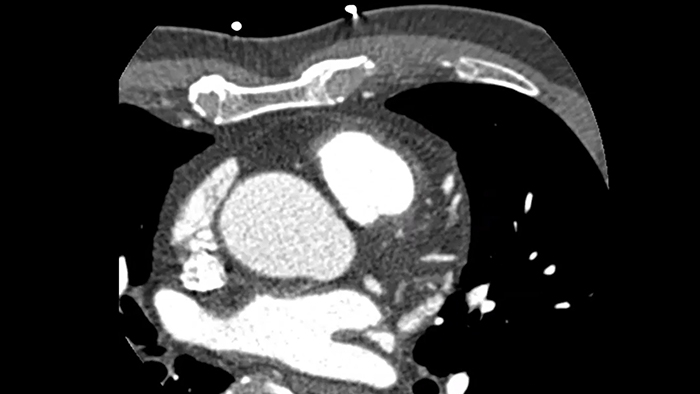

Supere los desafíos de las imágenes cardíacas

Imagenología cardíaca libre de movimiento que mejora la calidad de la imagen a altas frecuencias cardíacas

Precise Cardiac

Compensación del movimiento cardíaco